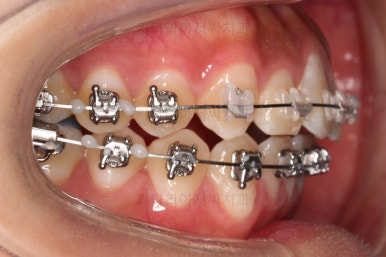

미니스크류를 식립을 하고요.

뒤로 뒤로 당겨줍니다.

만족하실 때까지 당겨줍니다.

교합도 신경 써주고요.

치열의 고른 느낌 좋고요.

덧니, 교합, 중앙선 등 모든게 좋아졌네요.